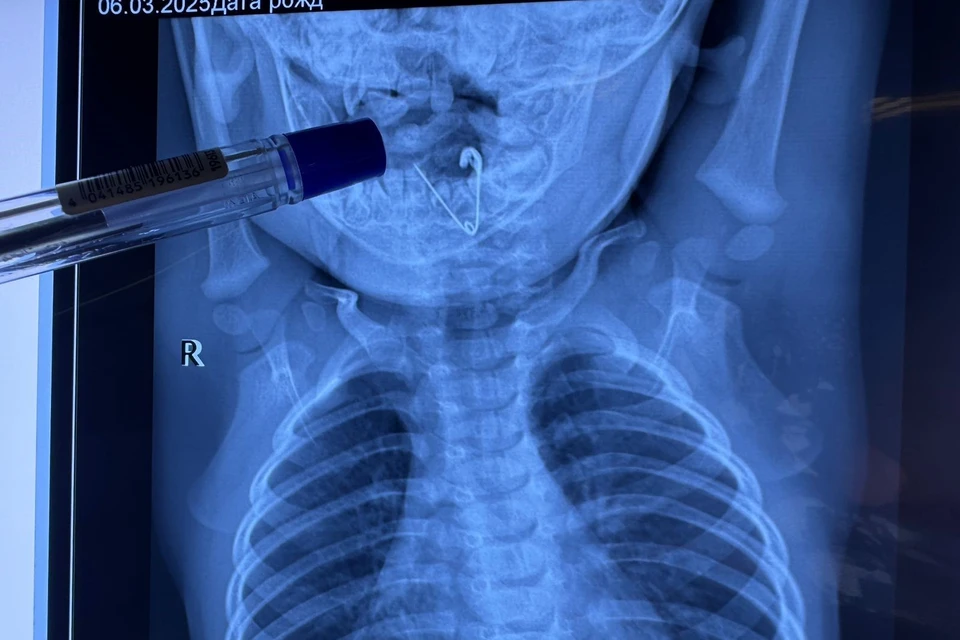

Невероятный случай спасения произошел в Краевой детской клинической больнице № 1 Приморья, где медики извлекли раскрытую булавку из гортани семимесячного мальчика. Сейчас ребенок чувствует себя хорошо и готовится к выписке, передает «Комсомольская правда – Дальний Восток» со ссылкой на telegram-канала «Детское здравоохранение Приморья».

После экстренной госпитализации в ЦРБ Черниговки и первичного рентгена, показавшего инородное тело, малыша оперативно доставили во Владивосток. В КДКБ № 1, где врачи обладают огромным опытом в подобных случаях, повторное рентгеновское исследование четко показало открытую булавку. Заведующая лор-отделением Светлана Таранова и заведующий эндоскопическим отделением Алексей Ткачук провели сложную операцию, аккуратно удалив булавку при помощи щипцов под контролем эндоскопической техники.